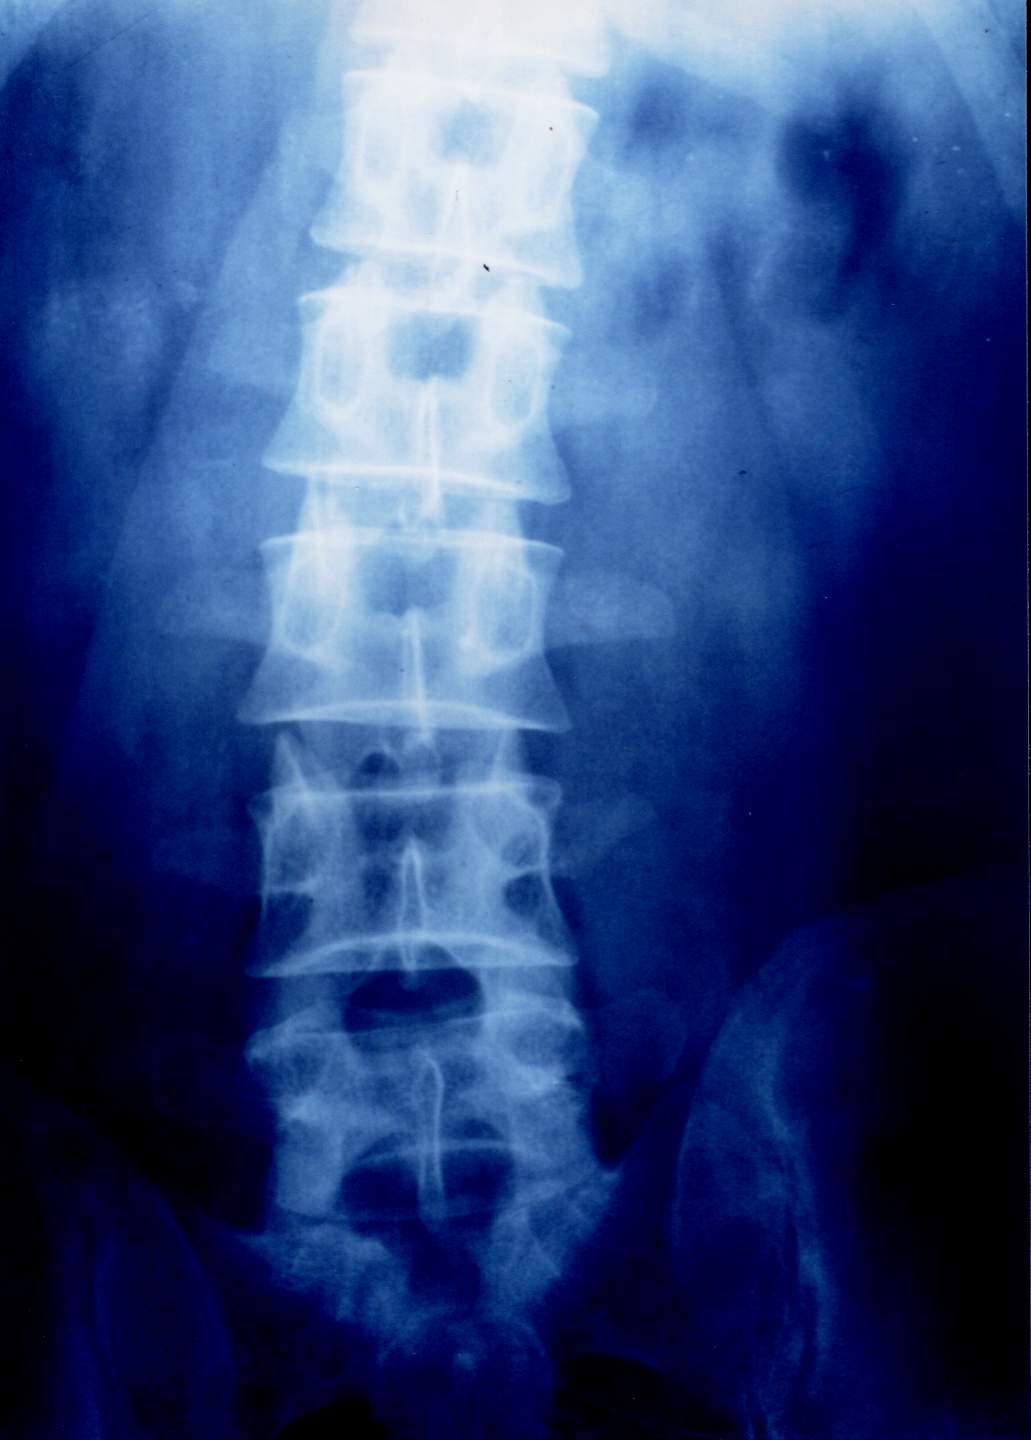

先来看看正常人体的脊柱整体情况,如下图:

请把头偏向右侧,侧着看我们的脊柱,是不是很像一条蜈蚣,千足之虫。而这蜈蚣一节一节的就叫做脊柱的椎体,根据部位的不同,分别称为颈椎、胸椎、腰椎以及屁股部位的骶骨、尾骨。

X线平片:对于骨科医生来说,一张简单便宜的X线片,往往比任何检查都重要,可以根据脊柱的弯曲度、椎间隙的变化,来间接推断出是否存在椎间盘突出,缺点是老百姓可能看得一头雾水,不知所以然!